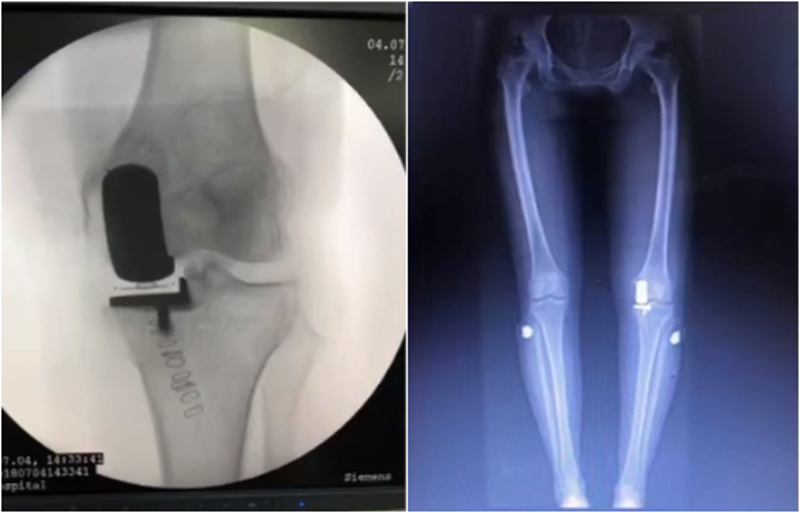

五、关于力线与假体位置——是否要求全长片?

牛津单髁课程表明,单髁只纠正关节内畸形,恢复下肢得病前的力线,不纠正关节外畸形。

但实际术后需要通过全长片来判断是否能取得好的力线,判断有无过度矫正或矫正不足的情况出现。还需要通过全长片区分内翻畸形的来源在哪里,是否能矫正,对适应证的选择有一定帮助。如果术后下肢整体力线外翻3°,则说明外侧间室压力明显升高。

小结:对于下肢整体力线,首先保证术后力线不能外翻,术后力线内翻不能超过10°,而术前关节外畸形不能超过10°。

除了下肢整体力线,还要考虑假体位置。理想状态下,假体位置对位好,力线轻度内翻。